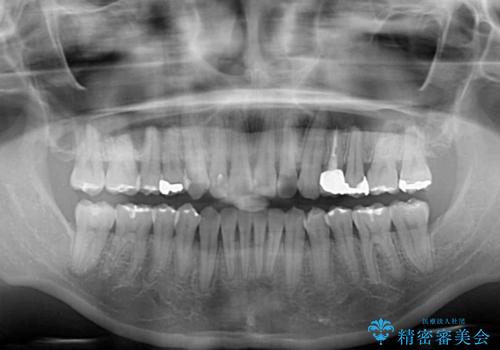

根管治療が必要な歯があったため、矯正治療前に根管治療を行い、その後はインビザラインにより矯正治療を行うこととしました。

矯正治療後には根管治療を行った歯の補綴治療を行うこととしました。

下顎の八重歯が上顎歯列に収まる過程で咬みにくさがありましたが、最終的には、咬み合わせも安定し、きれいに歯列を整えることができました。